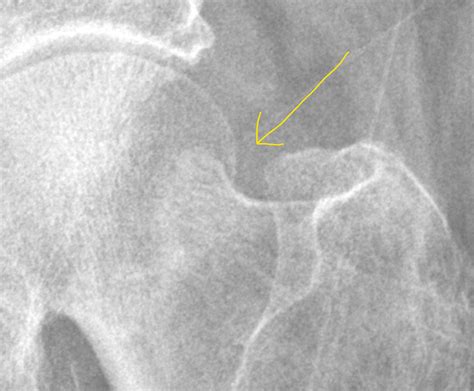

The impaction of fracture occurs when a bone sustains a high-energy impact that forces the fragments together, effectively "wedging" the bone tissue into itself. Unlike a transverse or oblique fracture where there is a clear break and separation, the impacted bone remains locked in a collapsed position. This is frequently seen in regions of the body characterized by cancellous (spongy) bone, such as the neck of the femur, the proximal humerus, or the wrist (distal radius).

Because the bone fragments are locked together, they may appear deceptively stable on initial physical examination. However, this inherent stability does not negate the severity of the trauma. The impaction often leads to shortening of the bone, alteration of joint mechanics, and potential damage to the surrounding blood supply, which is particularly critical in areas like the femoral neck.

• Femoral Neck: Often resulting from falls, these are critical due to the risk of avascular necrosis.

Diagnosing the impaction of fracture requires high-resolution imaging. A standard X-ray is the first line of defense, but it can occasionally miss the subtlety of the impaction if the viewing angle is not optimal. Orthopedic surgeons rely on specific radiographic views to identify the degree of angulation and the extent of bone compression.